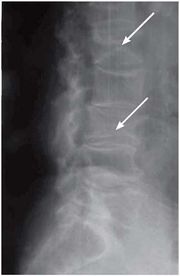

| 14:27, 14 августа 2017 | Bol spina13.jpg (файл) | 9 КБ | Рентгенография грудного отдела позвоночника. Компрессионный перелом тел L1- и L, позвонков на фоне остеопороза | 1 | |